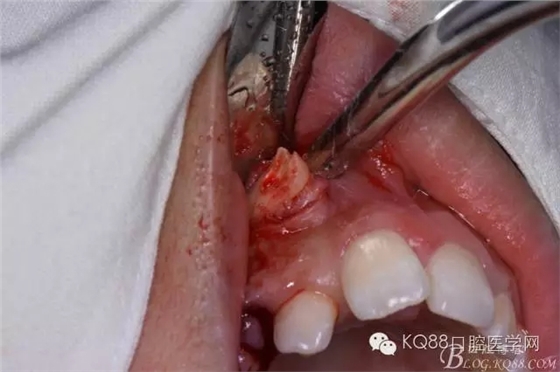

患者、女、高xx、17歲,主訴:外院轉(zhuǎn)診要求拔除埋伏牙。專科檢查:53殘根滯留、牙根斷面位于齦下,cbct檢查:13高位埋伏,牙冠壓迫12牙根的遠中面,牙根未見吸收,經(jīng)我院正畸科會診,建議拔除13、53,然后再正畸治療?;颊咄庵委煼桨?,術(shù)前簽知情同意書。 拔牙過程: 圖1.術(shù)前的cbct檢查:13位于12遠中根尖區(qū),13牙根接近上頜竇、53牙根滯留。 圖2.口內(nèi)觀:53滯留、牙根斷面位于齦下,12牙冠唇傾。 圖3.合面觀:12畸形舌側(cè)窩、腭側(cè)沒有明顯隆起 圖4.首先拔除53,然后在23唇側(cè)區(qū)域的前庭溝處的黏膜做弧形切口 圖5. 翻瓣 圖6.去骨 圖7.暴露出13牙冠 圖8.高速渦輪機分牙、目的是盡量少去骨。 圖9. 從頸部截分13 圖10. 13牙冠頸部分牙情況 圖11.再把牙冠分成近中、遠中兩部分。 圖12.取出13牙冠 圖14.取出13牙根 圖15.取出的13的牙根 圖16.拔除13牙后形成的拔牙創(chuàng)。 圖17.拔除的13. 圖18.縫合